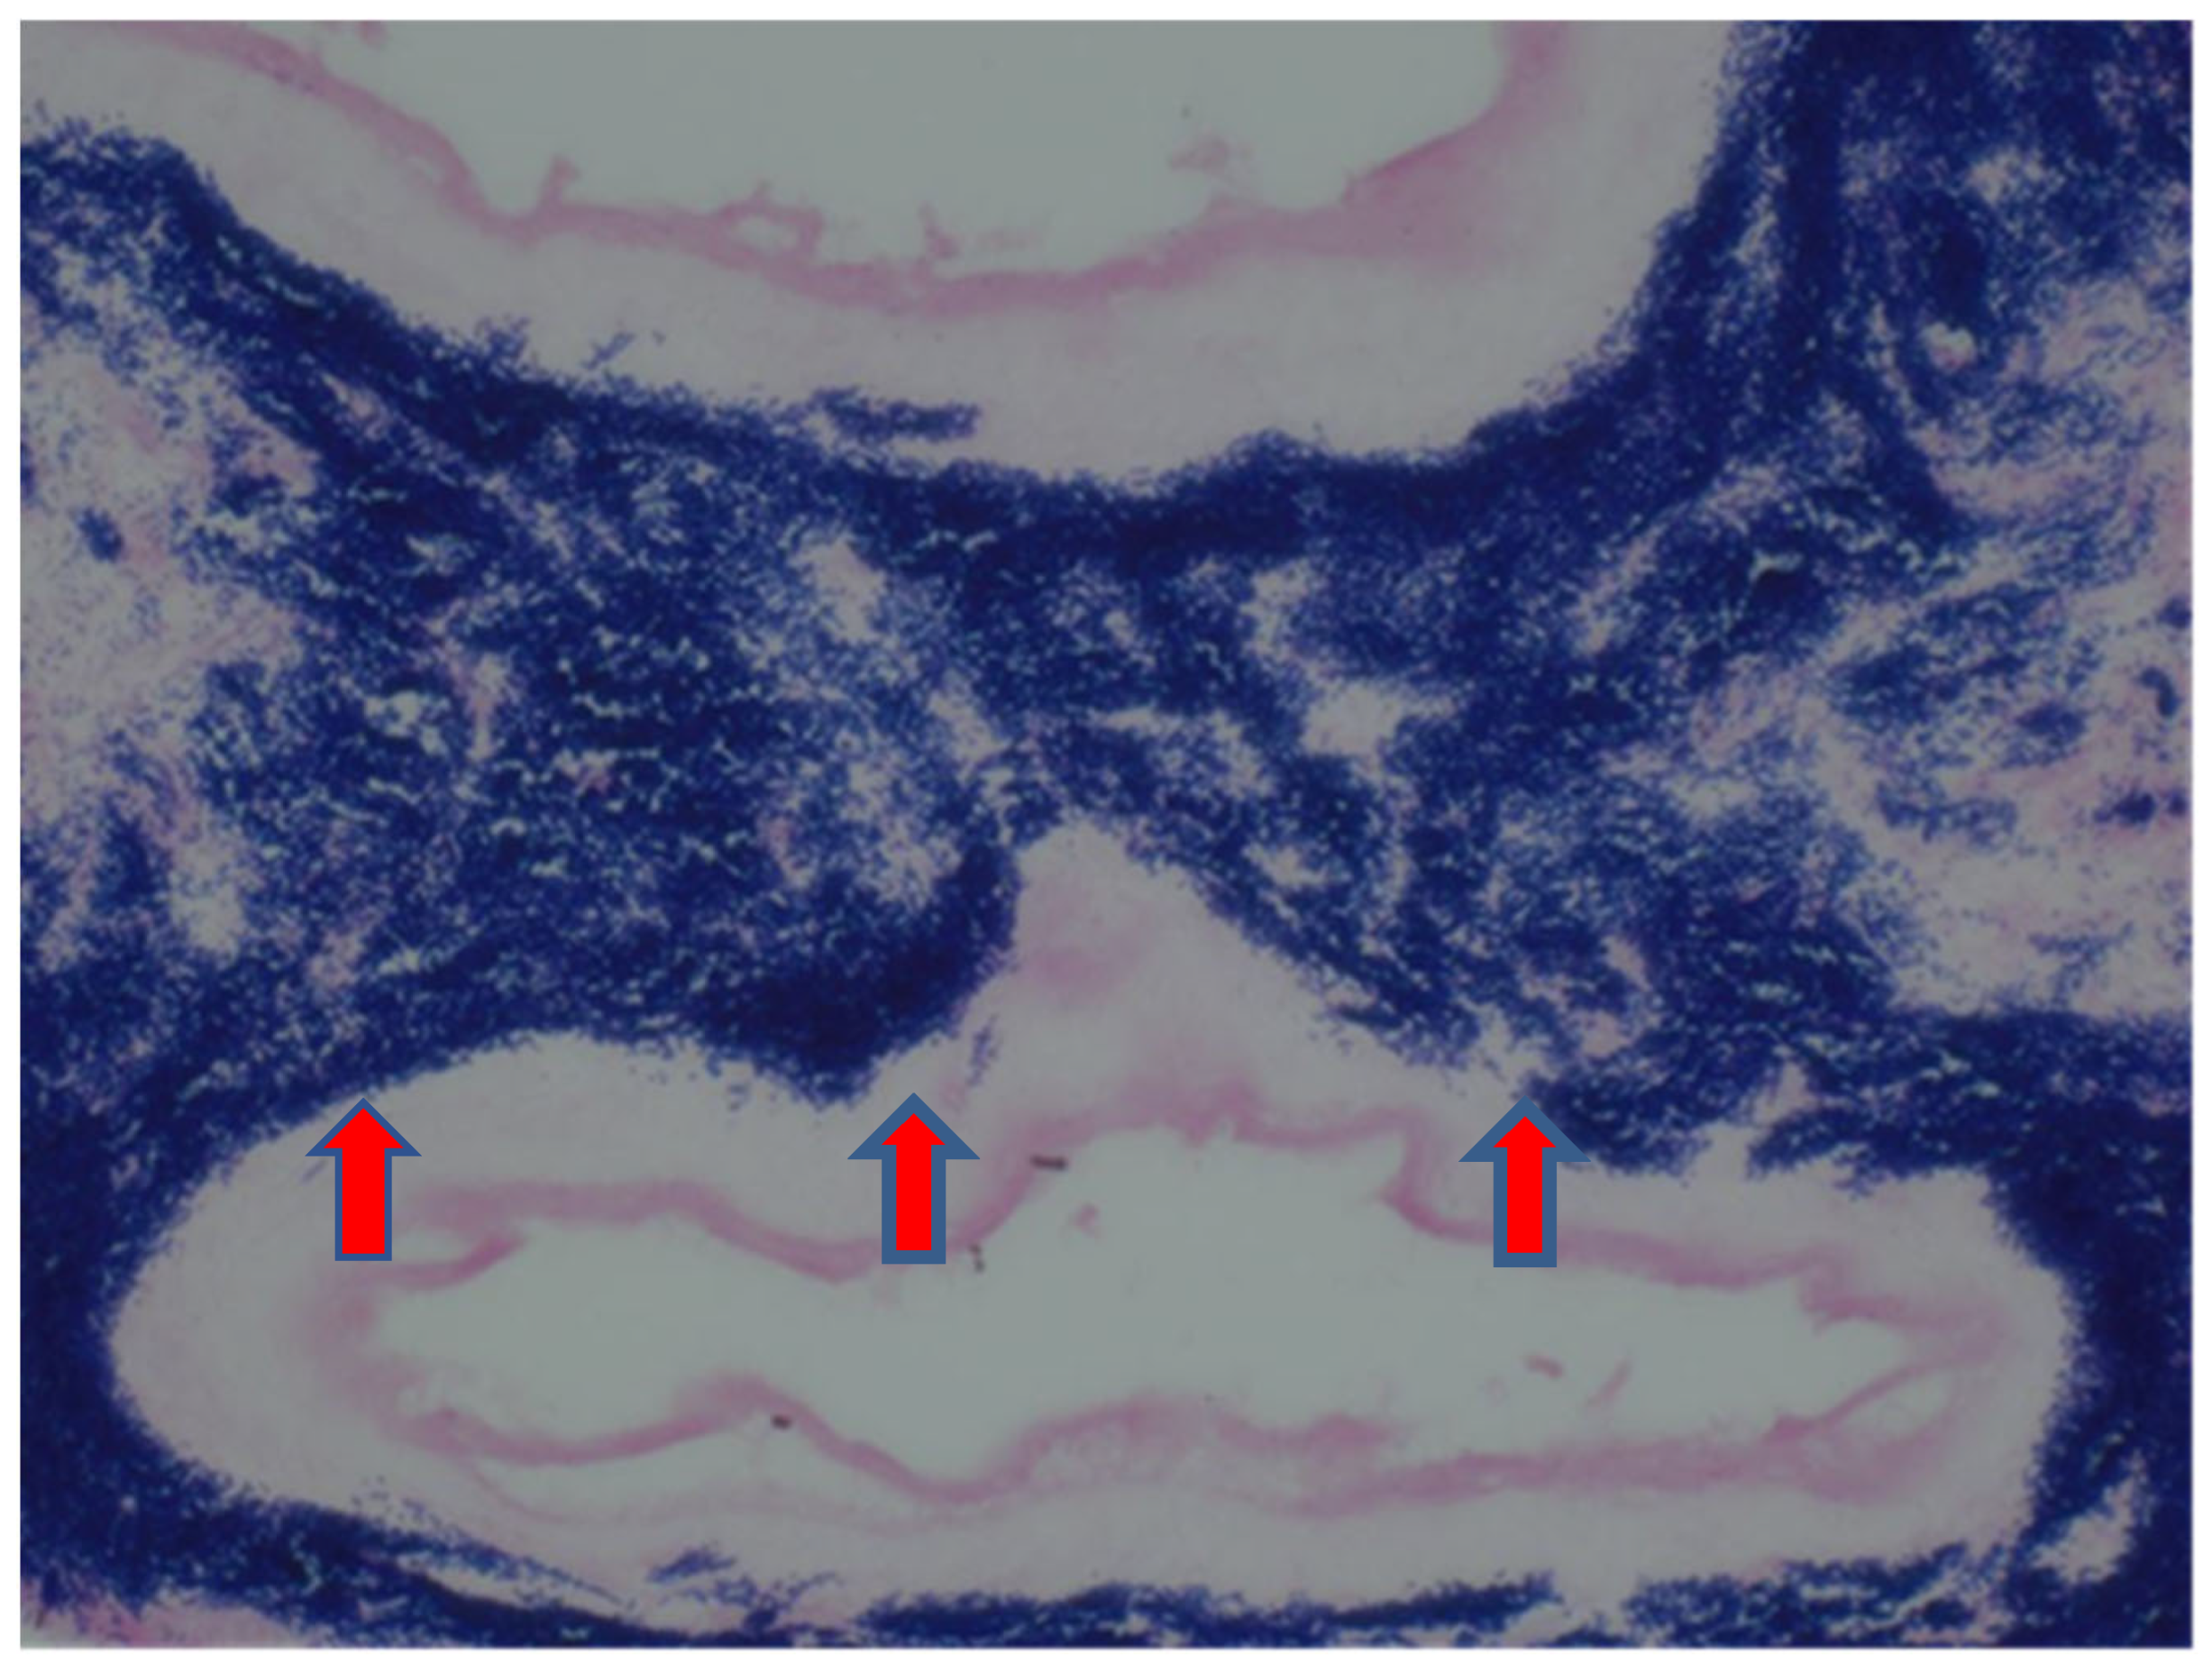

Figure 3.

Gram stain (400×) showing dense aggregates of Gram-positive organisms representing Actinomyces spp. (red arrows) in the placental membranes.